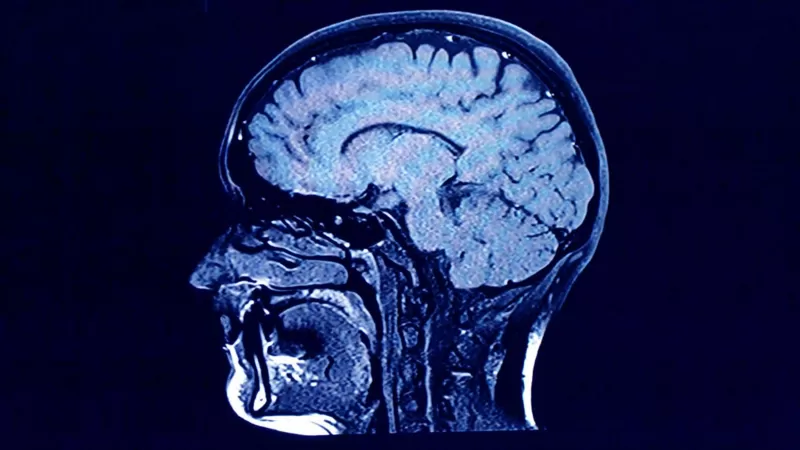

En 2013, el equipo también recurrió al pico de la bomba para observar la rotación de las células cerebrales.

Durante muchos años, los investigadores asumieron que la cantidad de neuronas se consolidaba en la infancia y, de hecho, su investigación anterior ya había sugerido que ese era el caso en regiones como la corteza.

Sin embargo, mediante el uso de carbono-14 para datar las neuronas dentro del hipocampo, confirmaron que se pueden producir nuevas neuronas a lo largo de la vida adulta.

Corroborada por otras investigaciones, la posible existencia de «neurogénesis adulta» ha sido uno de los descubrimientos neurocientíficos más importantes de los últimos 20 años.

Esto ha sugerido nuevas vías hacia estrategias médicas que podrían prevenir la pérdida de neuronas por enfermedad o incluso aumentar la generación de nuevas.